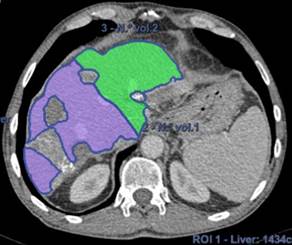

Por esto se realizó una volumetría hepática preoperatoria por TC, a fin de estimar el RHF, el mismo fue de 32% (Fig. 2 a) , sabiendo que en este paciente sería aceptable un mínimo de 30% dado que fue sometido a quimioterapia. (4

Se realizó TC de control a las 6 semanas de la cirugía en la cual no evidenció progresión tumoral y se comprobó una hipertrofia del RHF a 44% (Fig. 2b) , por lo que se decidió proceder al segundo tiempo.

Figura 2a: Volumetría inicial previo a primera hepatectomía. Violeta: hígado derecho, verde: FHR 32%.